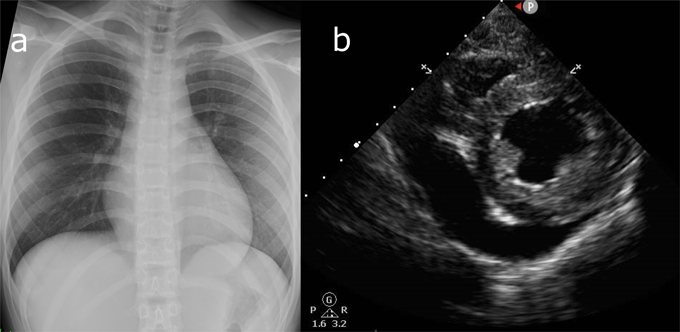

Her body temperature was 36.5°C, blood pressure 90/54 mmHg, heart rate 120/min, respiratory rate 28/min, and SpO2 100% in room air. A gallop rhythm was audible on auscultation of the heart, and extremities were cold. There was no hepatomegaly. A chest X-ray revealed no pneumonia or prominent cardiac enlargement (Fig. 1a). A blood test showed: white blood cell count 7,500/µL (neutrophil 78.5%, lymphocyte 18.6%, monocyte 2.8%), C-reactive protein 0.15 mg/dL, creatinine 1.02 mg/mL, creatine kinase (CK) 121 U/L, CK-myocardial band (MB) 4 U/L, and troponin-T 0.03 ng/mL, these suggesting myocardial damage and mild renal dysfunction.

Fig. 1 (a) Chest X-ray showing no evidence of pneumonia nor prominent enlargement of cardiac silhouette. (b) Echocardiography detected considerable pericardial effusion.

Dopamine (3 µg/kg/min) and milrinone (0.3 µg/kg/min) were introduced for LV dysfunction, and intravenous immunoglobulin (1.5 g/kg in total over 4 days), dexamethasone (0.1 mg/kg/day for 4 days), and remdesivir (100 mg/day for 4 days) were also administered. Six hours after admission, her blood pressure decreased to 80/60 mmHg. Echocardiography showed a considerable increase in pericardial effusion (Fig. 1b). Surgical drainage of the effusion was performed, and biochemical analysis revealed total protein of 5.9 g/dL, albumin of 3.8 g/dL, and lactate dehydrogenase of 226 U/L, suggesting that the fluid was of an exudative nature. No cellular components were found in the pericardial fluid. On the sixth day, her body temperature rose to 39.0°C, and C-reactive protein (0.95 mg/dL), CK (1768 U/L), and CK-MB (37 U/L) had peaked to their highest levels of the illness course. After the seventh day, no febrile episodes were noted, and the LV ejection fraction gradually improved to 57.1% by the ninth day. The patient returned home in a healthy condition on the 20th day.